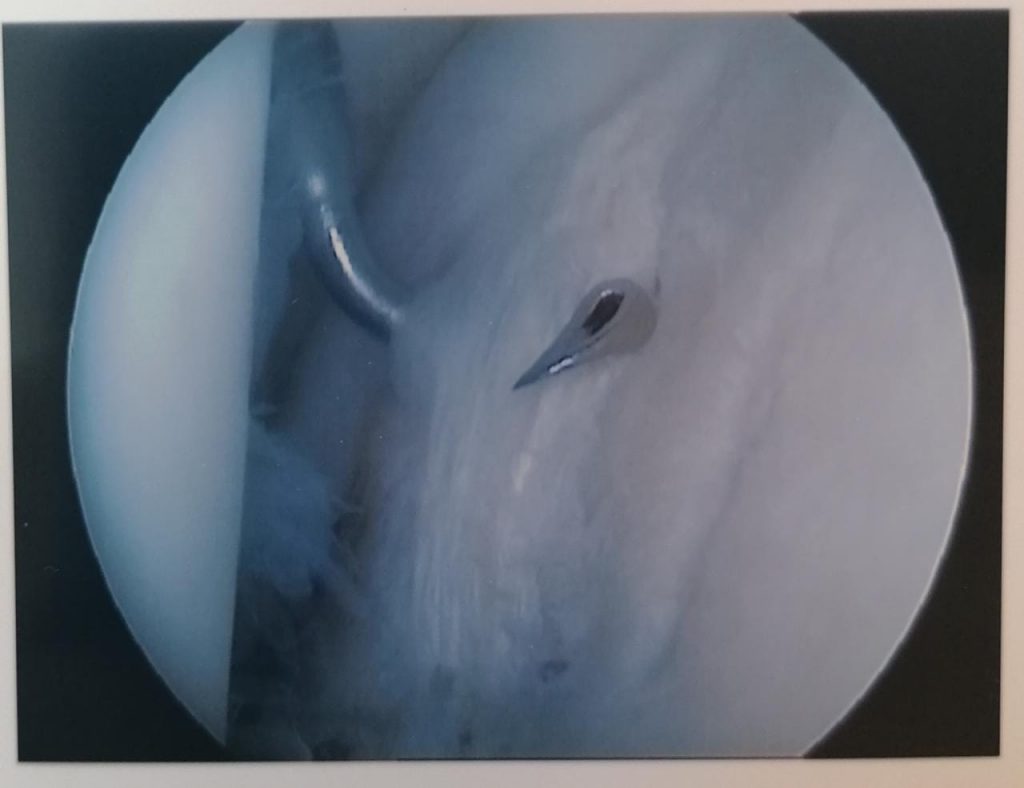

One common problem is a tear of the capsule where it adheres to the shoulderblade part of the joint. This is called a Bankart lesion and can be to the front or the back of the joint. Repair is done arthroscopically using anchors. The outcome of this method is usually very good. Recovery takes about six weeks with the physio being continuously involved.

Above are pictures showing the placement of a suture through the edge of the capsule (labrum) to the placement of the anchor as well as the end result. All of this happens through two small incisions.